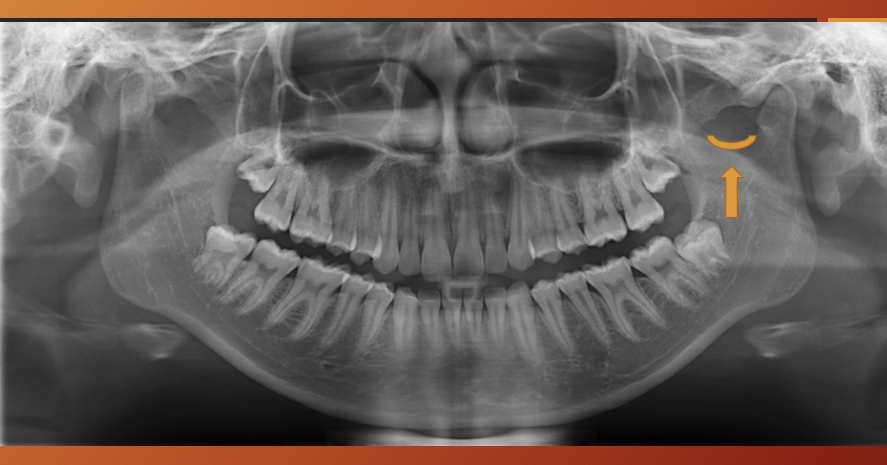

What has happened to the maxillary sinus in this image?

pneumatization - physiological process of expansion of sinus wall into surrounding bone , usually in an area where teeth have been lost prematurely